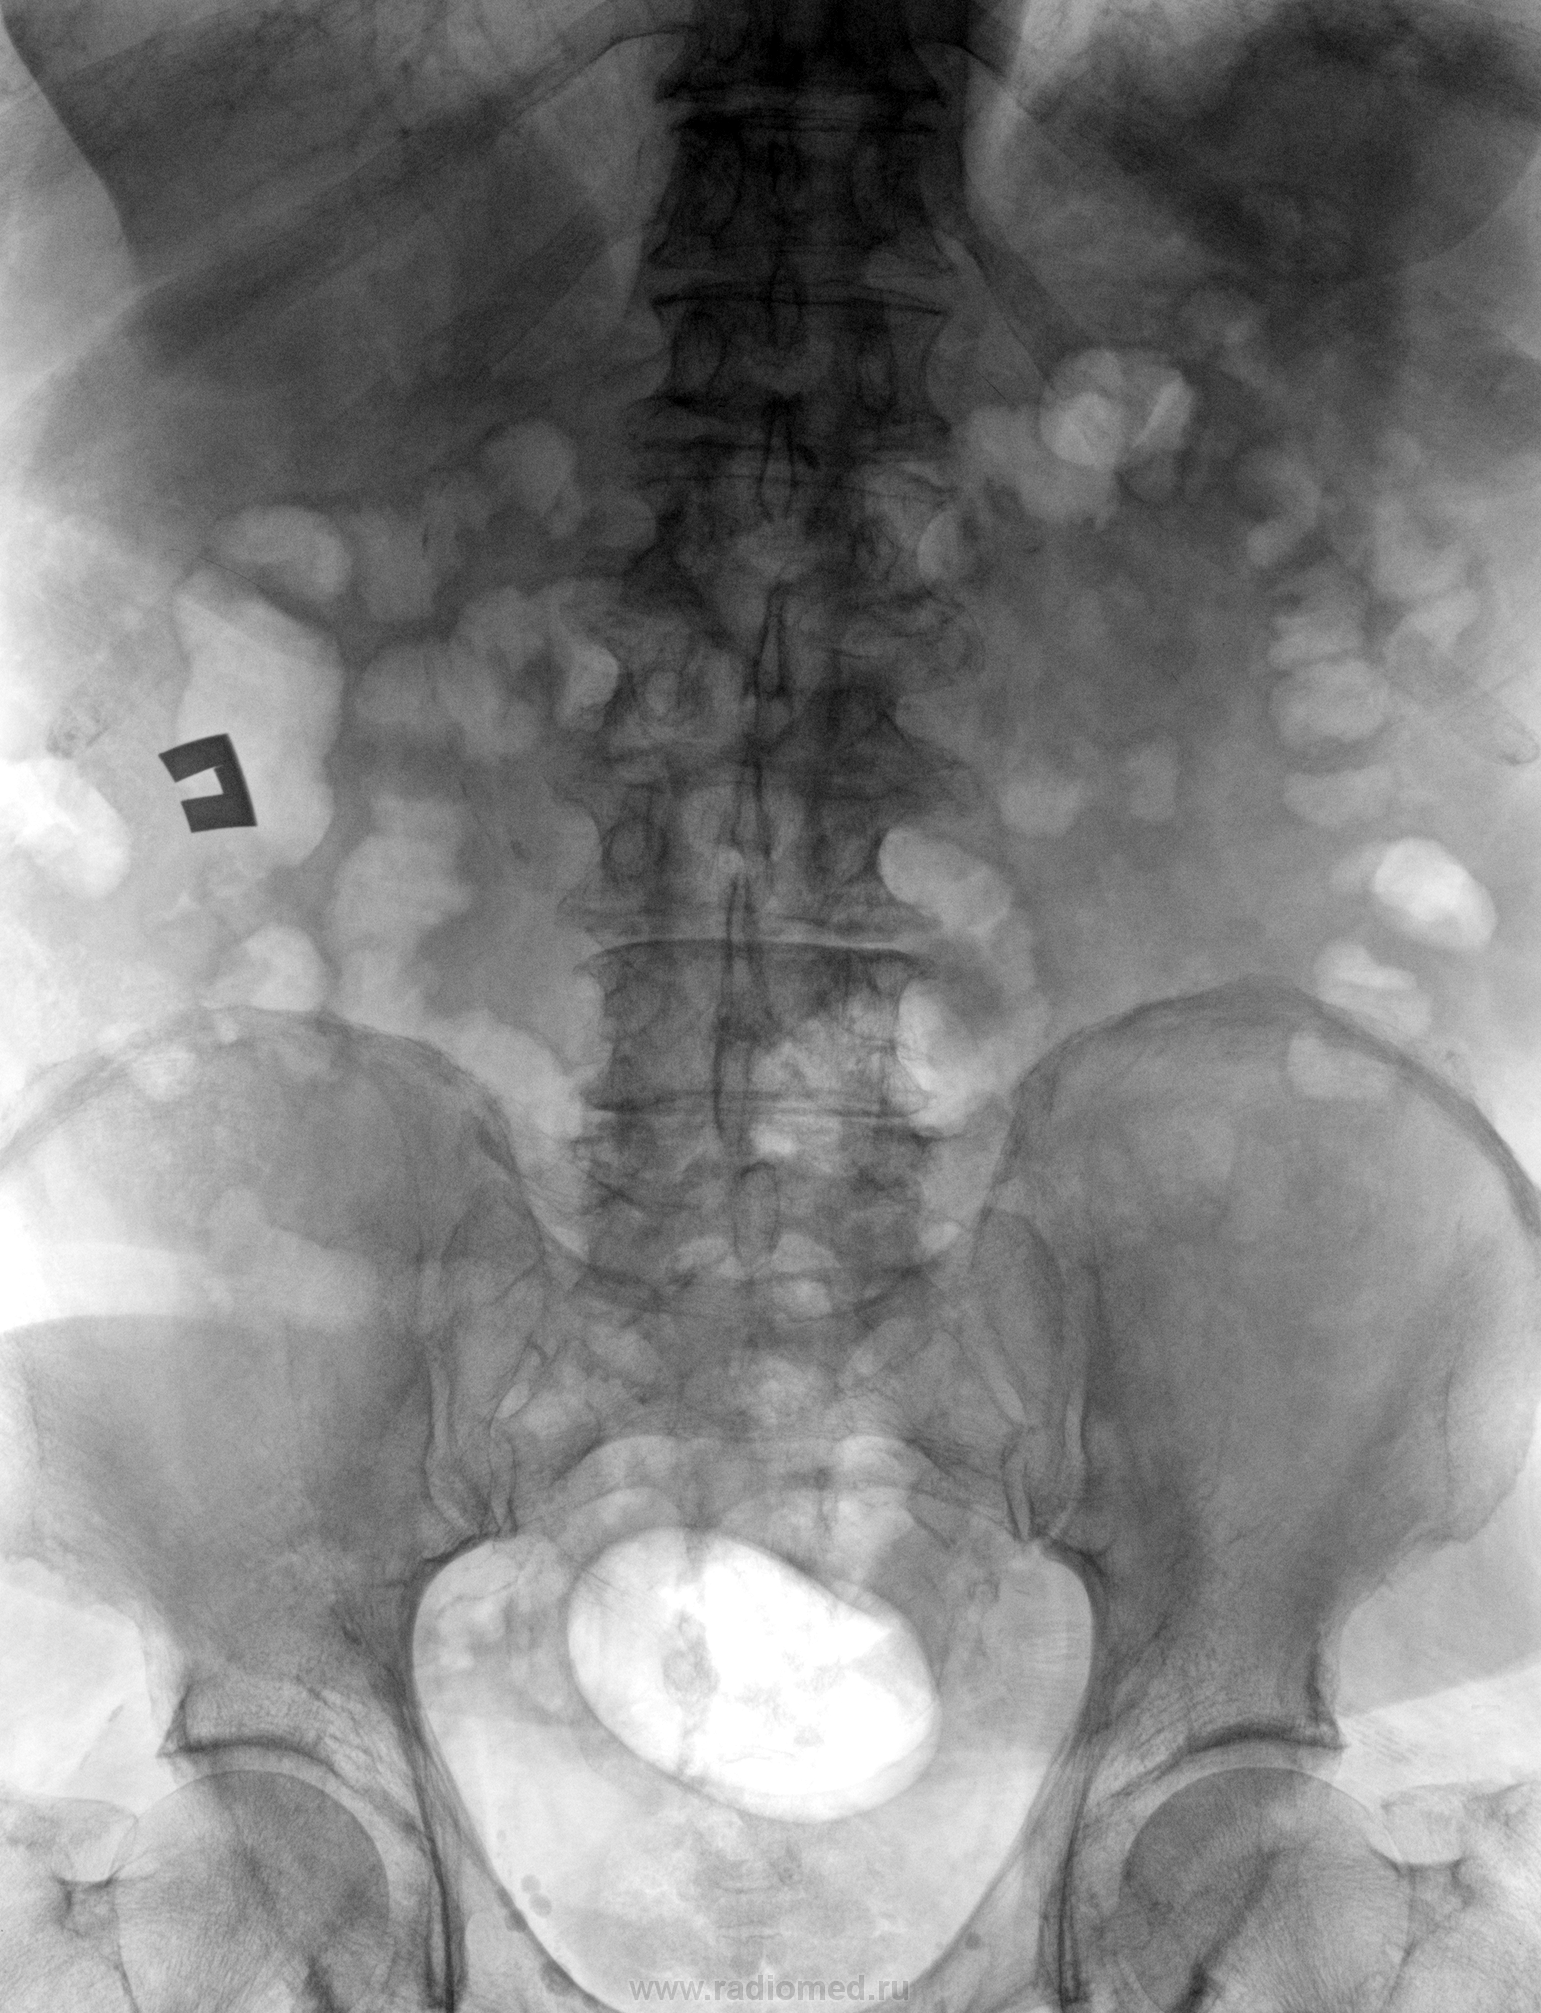

С какой стороны колика-то? Если справа, то там есть тень, "подозрительная на конкремент" (красная стрелка). Да смущают ещё тенёчки, отмеченные жёлтым.

Возможно, я бы придрался к тени "характера конкремента", возможно, желтая стрелка, по более пристально, я - бы рассматривал "цепочку" отмеченную красными стрелками.

А если раскрутить эти "цепочки", что получиться? Колика якобы правосторонняя.

Да, это может быть что угодно, в том числе и расслаивающаяся аневризма.

Похоже на обызвествление края аневризмы!

Вот мне тоже показалось, что "цепочка" -- но если рассматривать её так широко, как Вы отметили (хотя лично мне две последние, нижние кажутся сомнительными), то к мочевыводящим путям её никак "не пристегнешь". Обызвествление стенки чего-то полого?

Аневризма абдоминального отдела аорты с прорывом забрюшинное пространство и образованием гематомы, от подпеченочного пространства до малого таза.

Кстати сейчас пролистывая литература, нашел аналогичный случай.